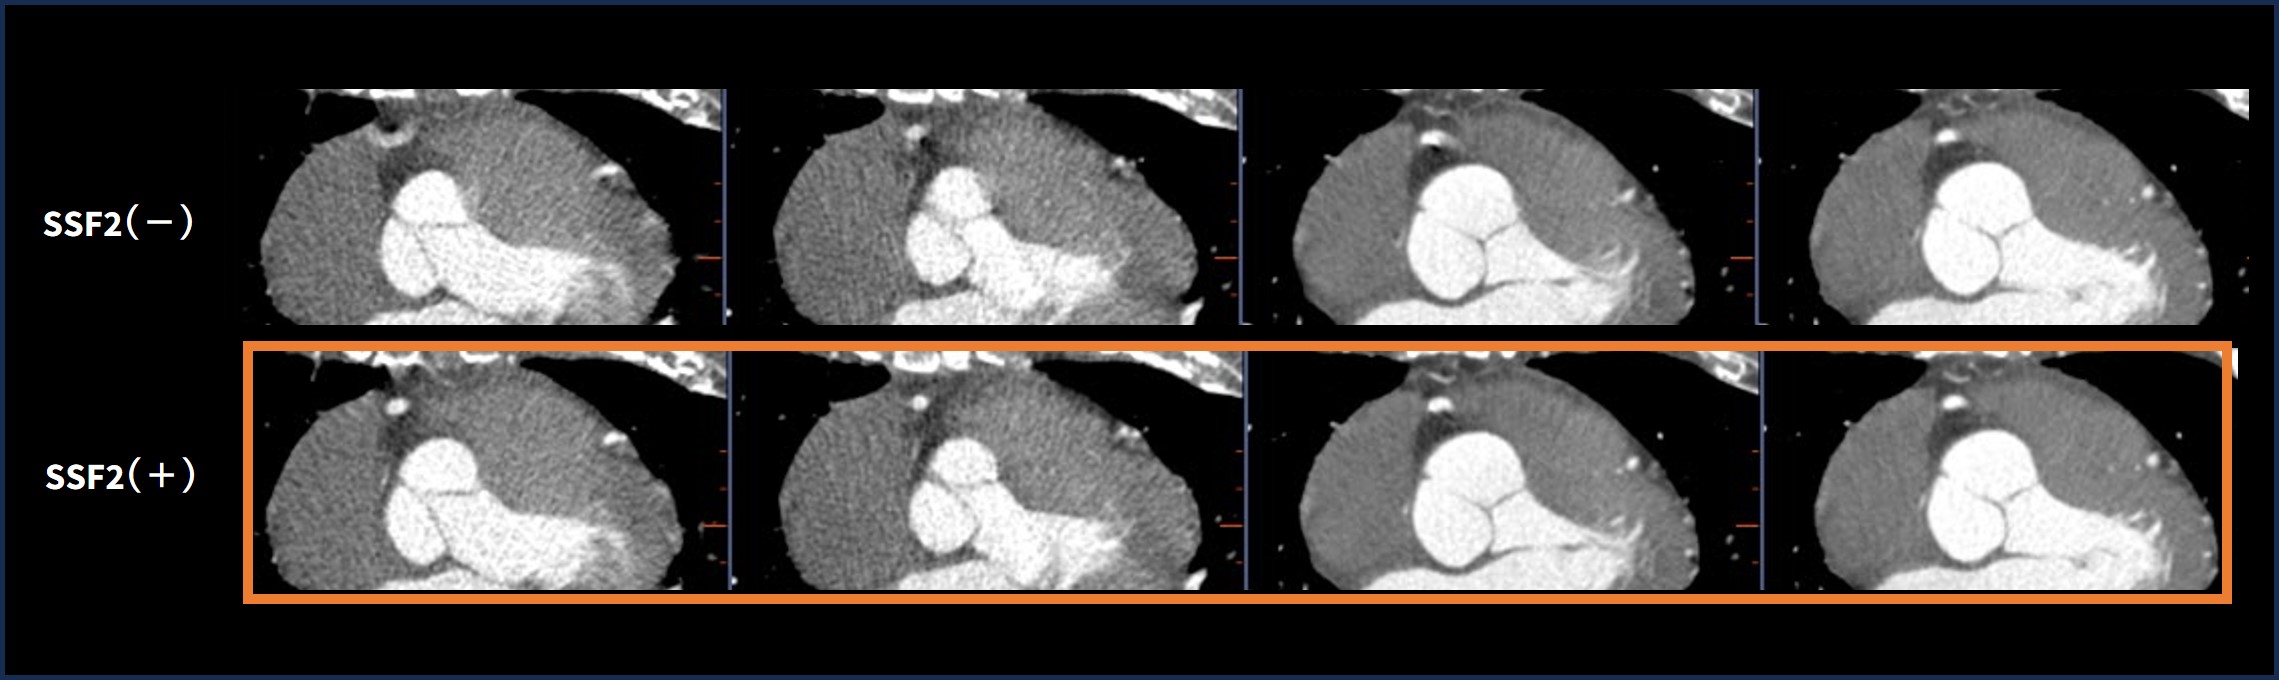

症例2) 20%/40%/60%/80%におけるRCA中間部でのSSF2の動態補正

20%/40%/60%/80%のそれぞれのPhaseでRCA中間部におけるSSF2の有無で比較した例である。(Fig.4 )

SSF2をかけた画像はどの時相でも全くMotion artifactを認めない。

Fig.4 各Phase(20%/40%/60%/80%)におけるSSF2ありなし比較